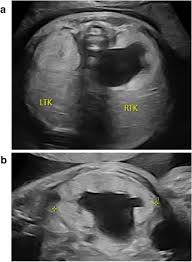

Echogenic Kidneys, also called hyperechogenic kidneys, appear brighter than usual during a mid-trimester ultrasound scan. This finding may be a singular occurrence or linked to a number of underlying kidney disorders.